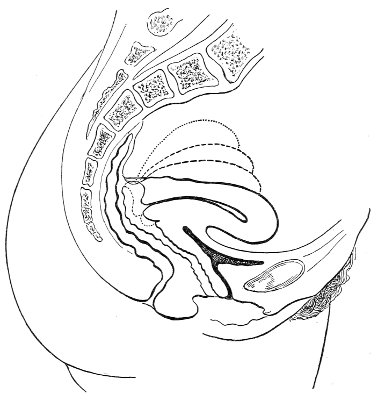

Fig. 3.—Bimanual examination; median sagittal section of the pelvis.

In making the bimanual examination the structures 25 should be palpated methodically in order. The vaginal finger notes the condition of the cervix uteri. If the fundus be in the normal position, the uterus can then be taken between the abdominal hand (upon the fundus) and the vaginal finger (upon the cervix) (Fig. 3). The shape, size, mobility, and consistency are noted. The vaginal finger is then passed anteriorly and laterally toward either uterine cornu, while the abdominal fingers pass over to the posterior aspect of the same cornu. The ovarian ligament and the proximal end of the Fallopian tube may thus be felt. Passing farther outward, the whole of the tube and the ovary may be examined. The same procedure is then applied to the opposite side.

Vaginal and Bimanual Examination.—Having examined and noted the condition of the external genitals, the physician should next proceed to examine the vagina. The index finger of the right or the left hand should be gently introduced into the vagina. The condition of the vaginal walls, and the direction, consistency, form, etc. of the vaginal cervix, may be determined. The shape and size of the os uteri should be noted. The ulnar edge and the tips of the fingers of the other hand should then be placed upon the abdomen, immediately above the symphysis pubis, and gently pressed backward and downward toward the vaginal finger 24 (Fig. 2). In this way the various pelvic organs, the uterus, Fallopian tubes, ovaries, and ureters, may be palpated between the two hands, and their position, size, shape, and consistency may be determined. Such an examination is, of course, made much more easily in a thin woman than in a fat one. A thin woman a few weeks after labor may be examined most easily, on account of the relaxation of the abdominal and vaginal walls.